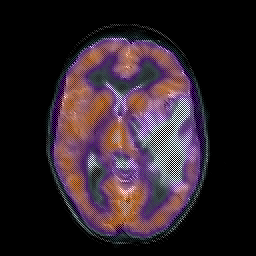

Metastatic bronchogenic carcinoma, overlay -- Slice #10

[Home][Help][Clinical] Slice 10